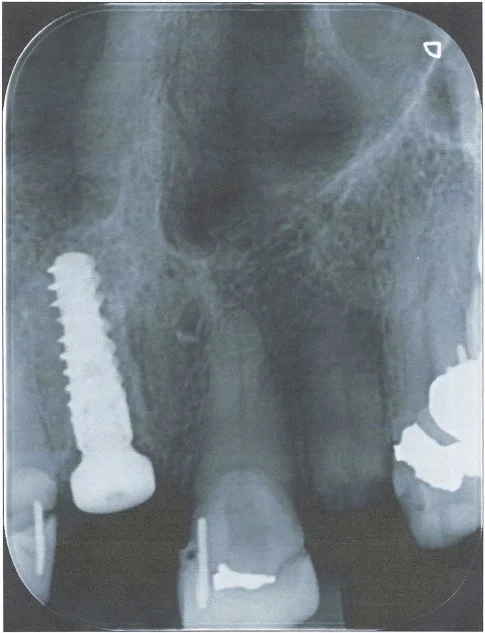

This 60 year old lady had recurring problems with the top right crowned front tooth which was restored with a gold post crown. This post was short and angled and the post crown kept on debonding from the root and the post crown kept falling out of her mouth. Eventually decay ensued and the root cracked as illustrated in the radiograph.

-

The patient was referred to me in 2021 at Lismore and I referred the patient to a Periodontist in Brisbane. He extracted the tooth, placed a temporary partial denture plate to fill the space and subsequently placed a Straumann implant fixture and healing cap

I completed this case at Lismore in 2022 and this radiograph illustrates the completed the screw accessible zirconia implant crown